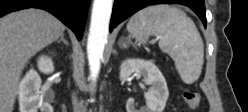

Мультиспиральная компьютерная томография селезенки – высокоинформативный лучевой метод исследования, основанный на использовании рентгеновского излучения и позволяющий детально визуализировать паренхиму селезенки, состояние близлежащих органов и тканей, питающих ее кровеносных сосудов и регионарных лимфоузлов.

МСКТ селезенки проводится как с использованием контраста, так и без него. Контрастирование применяется для выявления патологических очагов, которые могут быть не видны при нативном исследовании. Для этого внутривенно вводится контрастный препарат, содержащий йод и накапливающийся в патологических очагах опухолевой и воспалительной природы.

Мультиспиральная компьютерная томография селезенки с внутривенным болюсным контрастированием используется в диагностике гематологических заболеваний, опухолевых процессов, при планировании хирургического вмешательства и для отслеживания эффективности лекарственной терапии.

• кисты;

• доброкачественные и злокачественные опухоли, а также метастатическое поражение органа;

• сосудистые опухоли;

• кальцификаты;

• изменения воспалительного характера;

• гнойные и некротические процессы;

• нарушения кровоснабжения;

• травмы органа;

• инфаркт селезенки

• патологии сосудов.